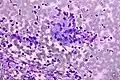

Adenocarcinoma colorrectal. Tinción de Field . -